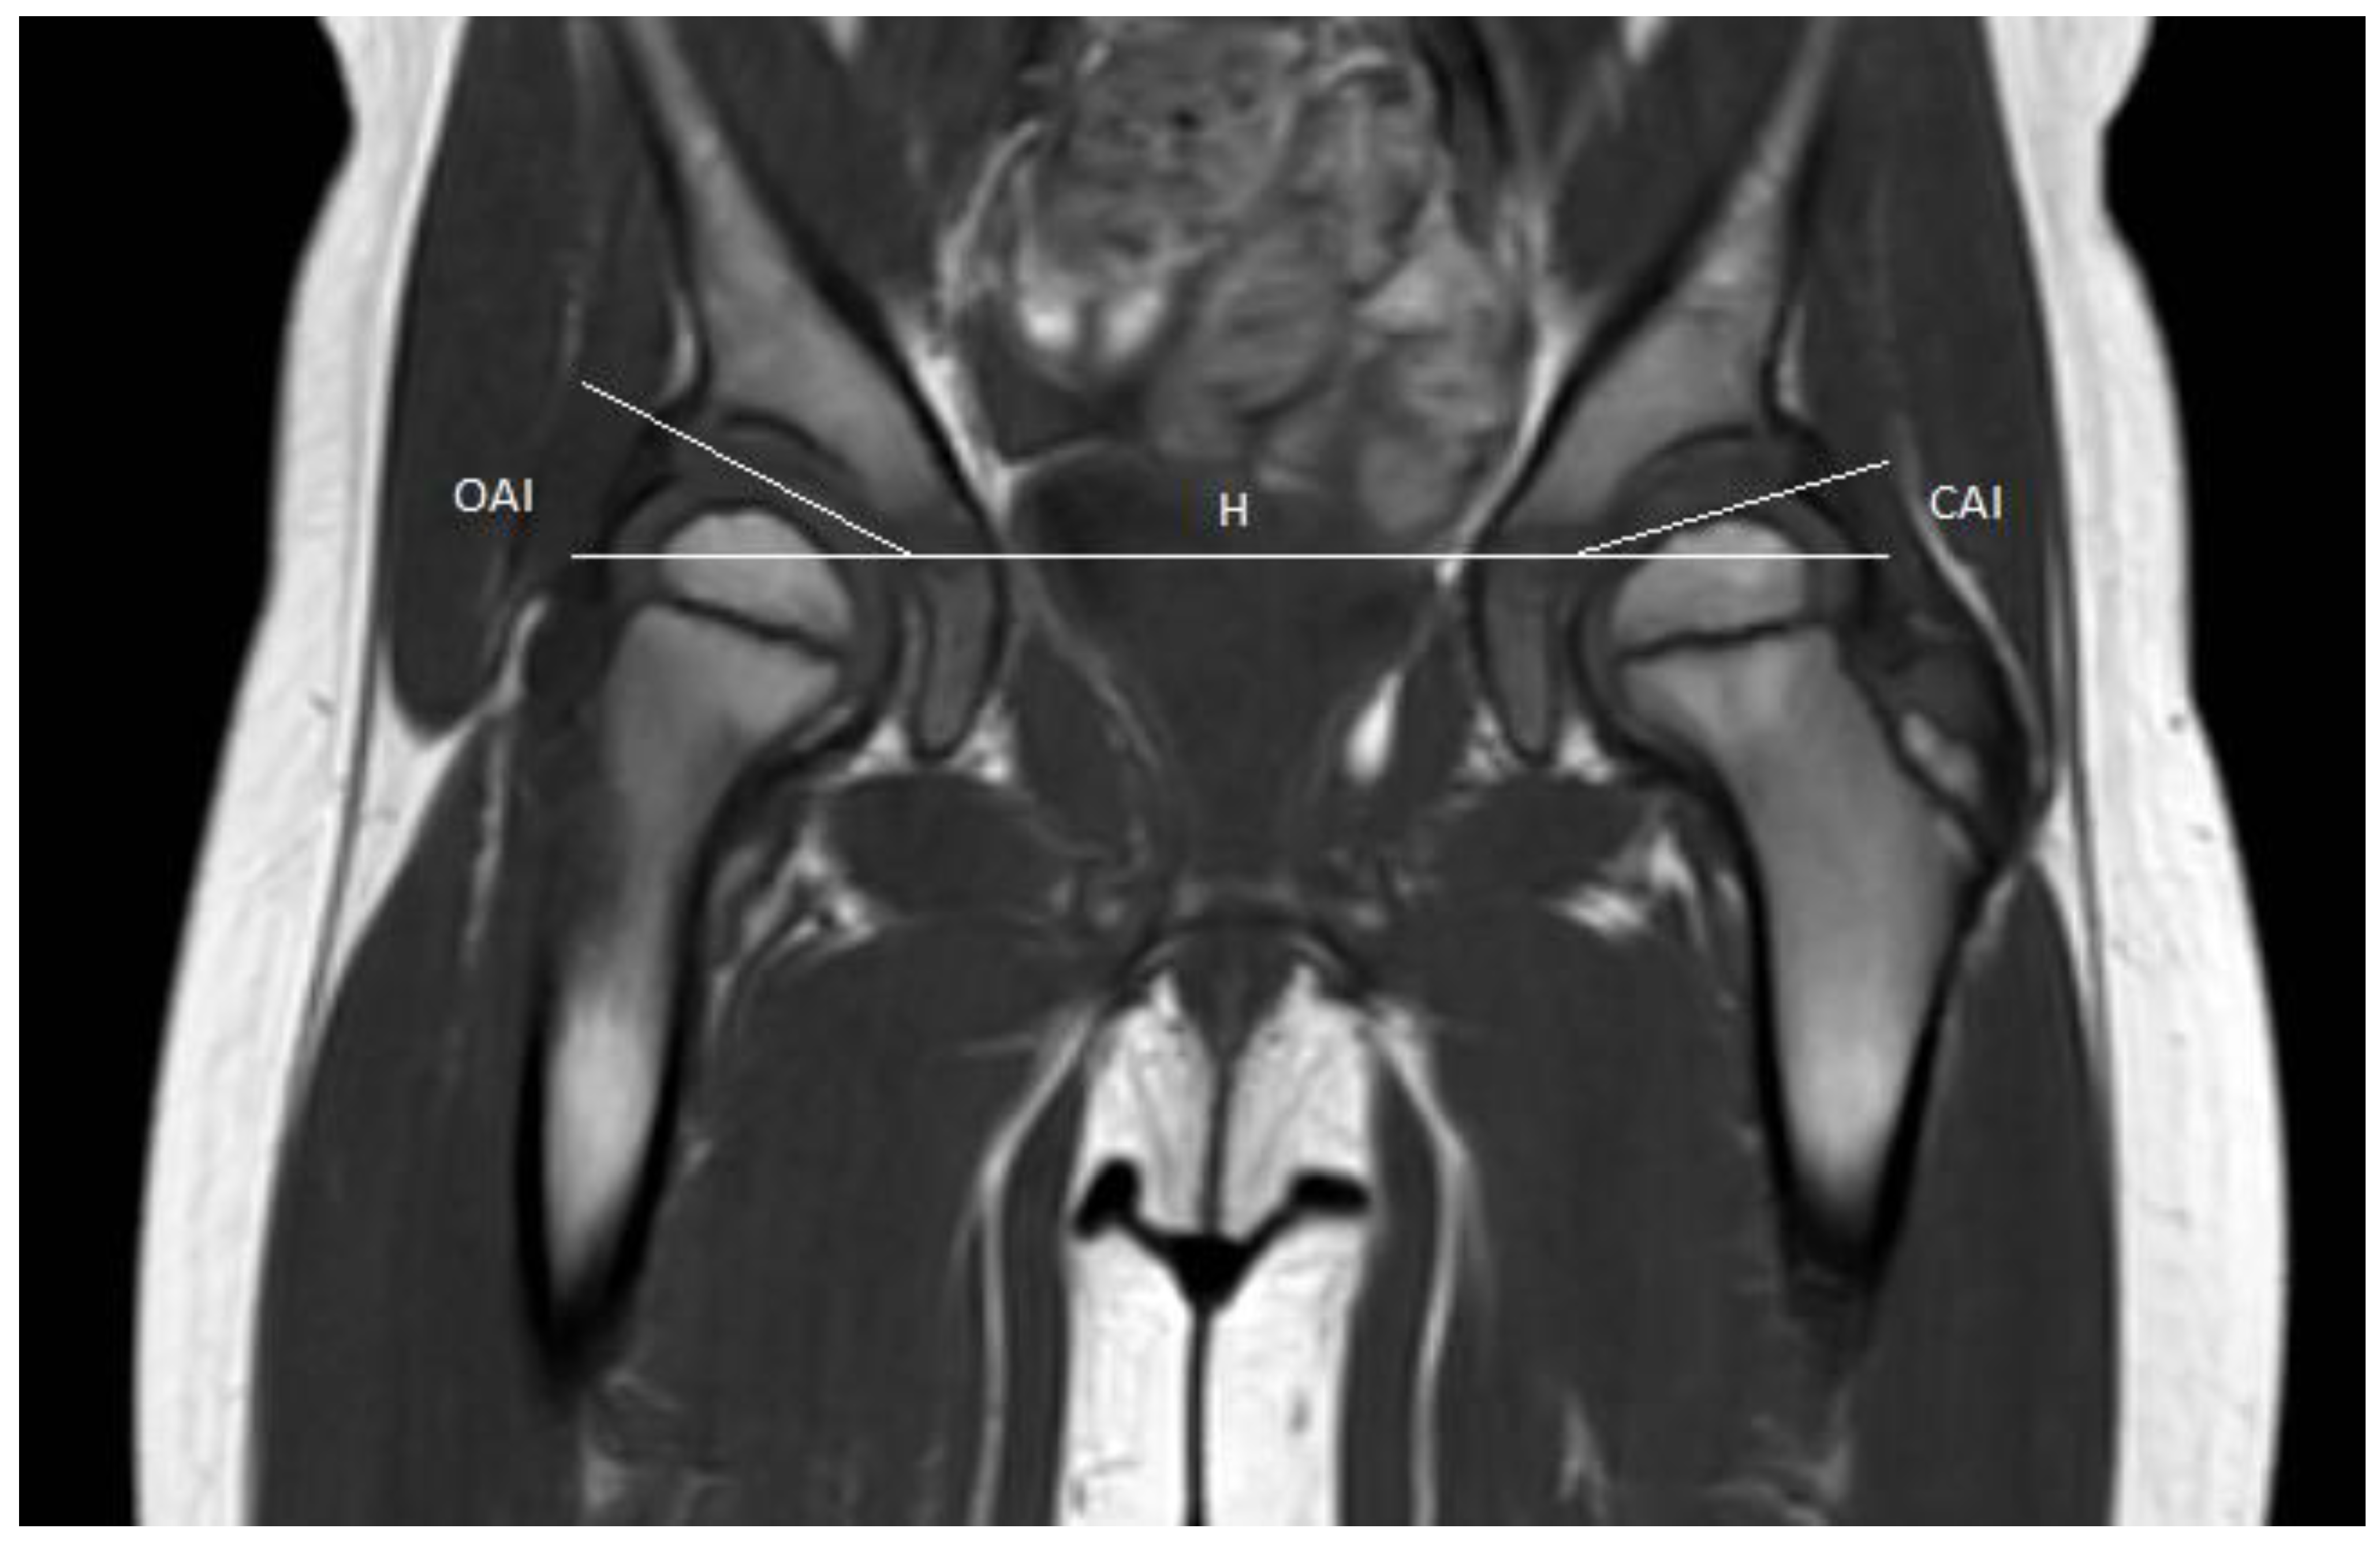

Measurements were performed retrospectively on T1-weighted pelvic MRI scans and pelvic radiographs. The raters measured the osseous acetabular indexes (OAI), according to the method described by Tönnis [9]. The cartilaginous acetabular index (CAI) was measured on MRI scans, according to the description by Zamzam et al. [4], as the angle between Hilgenreiner’s line and a line drawn from the lateral margin of the cartilaginous acetabulum at the attachment of the labrum to the superolateral margin of the triradiate cartilage (Figure 1).

T1 weighted coronal magnetic resonance image scan of a paediatric pelvis. H: Hilgenreiner’s line; OAI: Osseous acetabular index; CAI: cartilaginous acetabular index. CAI was measured as the angle between Hilgenreiner’s line and a line drawn from the lateral margin of the cartilaginous acetabulum at the attachment of the labrum to the superolateral margin of the triradiate cartilage.